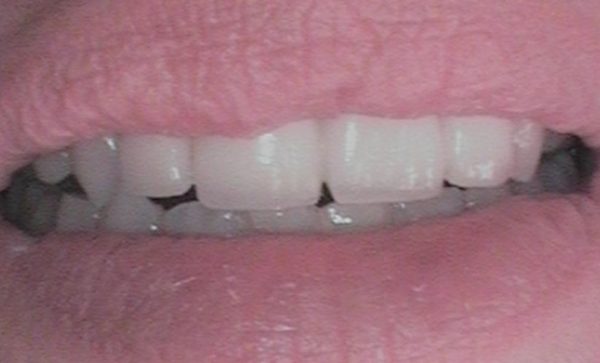

Case 40